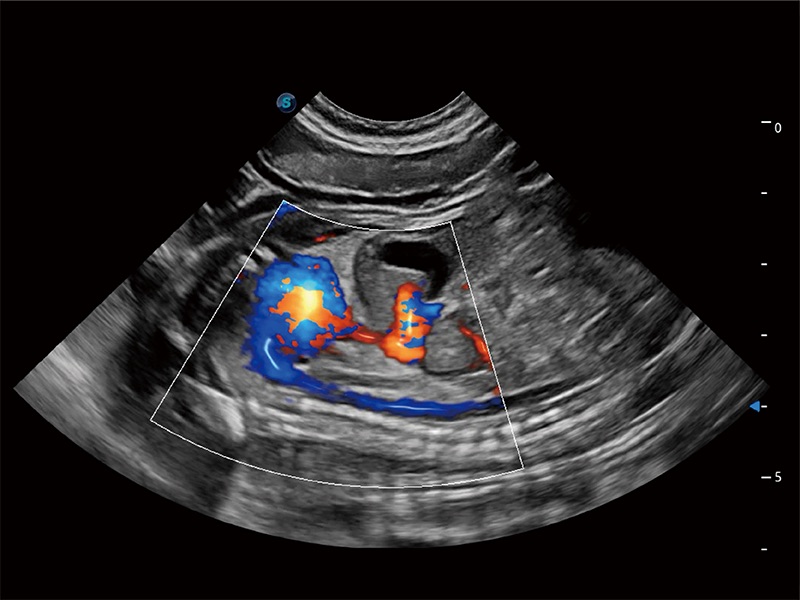

极大提升超低速微细血流的检出能力,同时更精准地滤除软组织和超声信号,为兽用医生提供以往无法通过常规血流获得的疾病诊断信息。